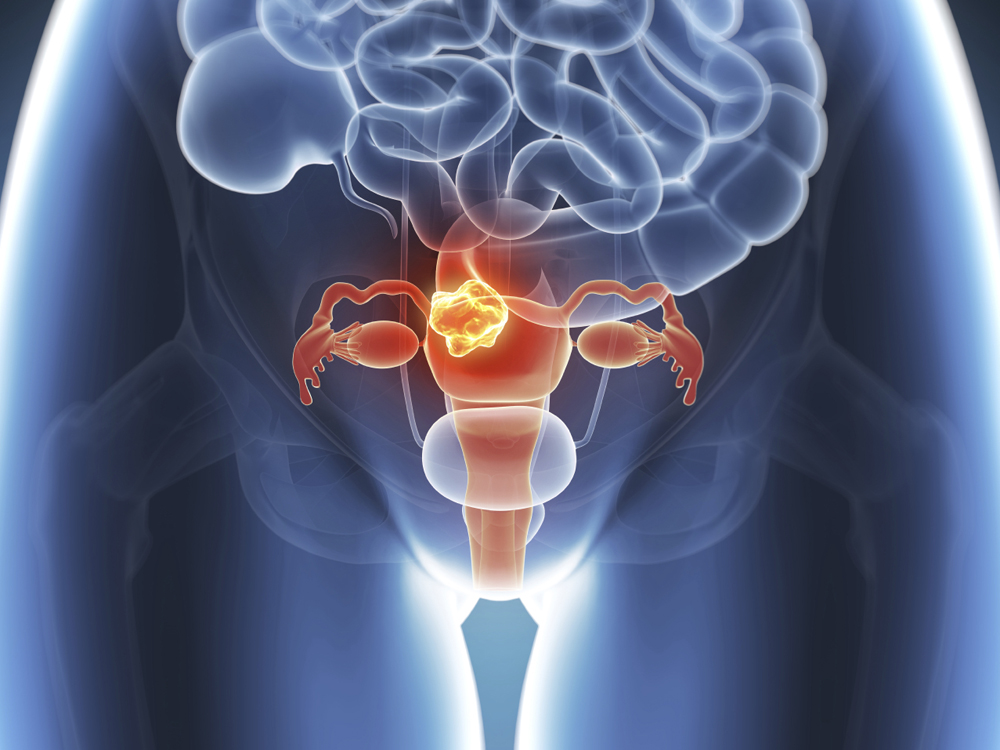

El síndrome de ovario poliquístico cambia de nombre: ahora será reconocido como un trastorno metabólico y endocrino

Durante años, millones de mujeres vivieron síntomas como menstruaciones irregulares, acné severo, infertilidad, aumento de peso o fatiga crónica sin obtener un diagnóstico claro. La razón: muchas no presentaban quistes visibles en los ovarios, pese a padecer el llamado síndrome de ovario poliquístico (SOP).